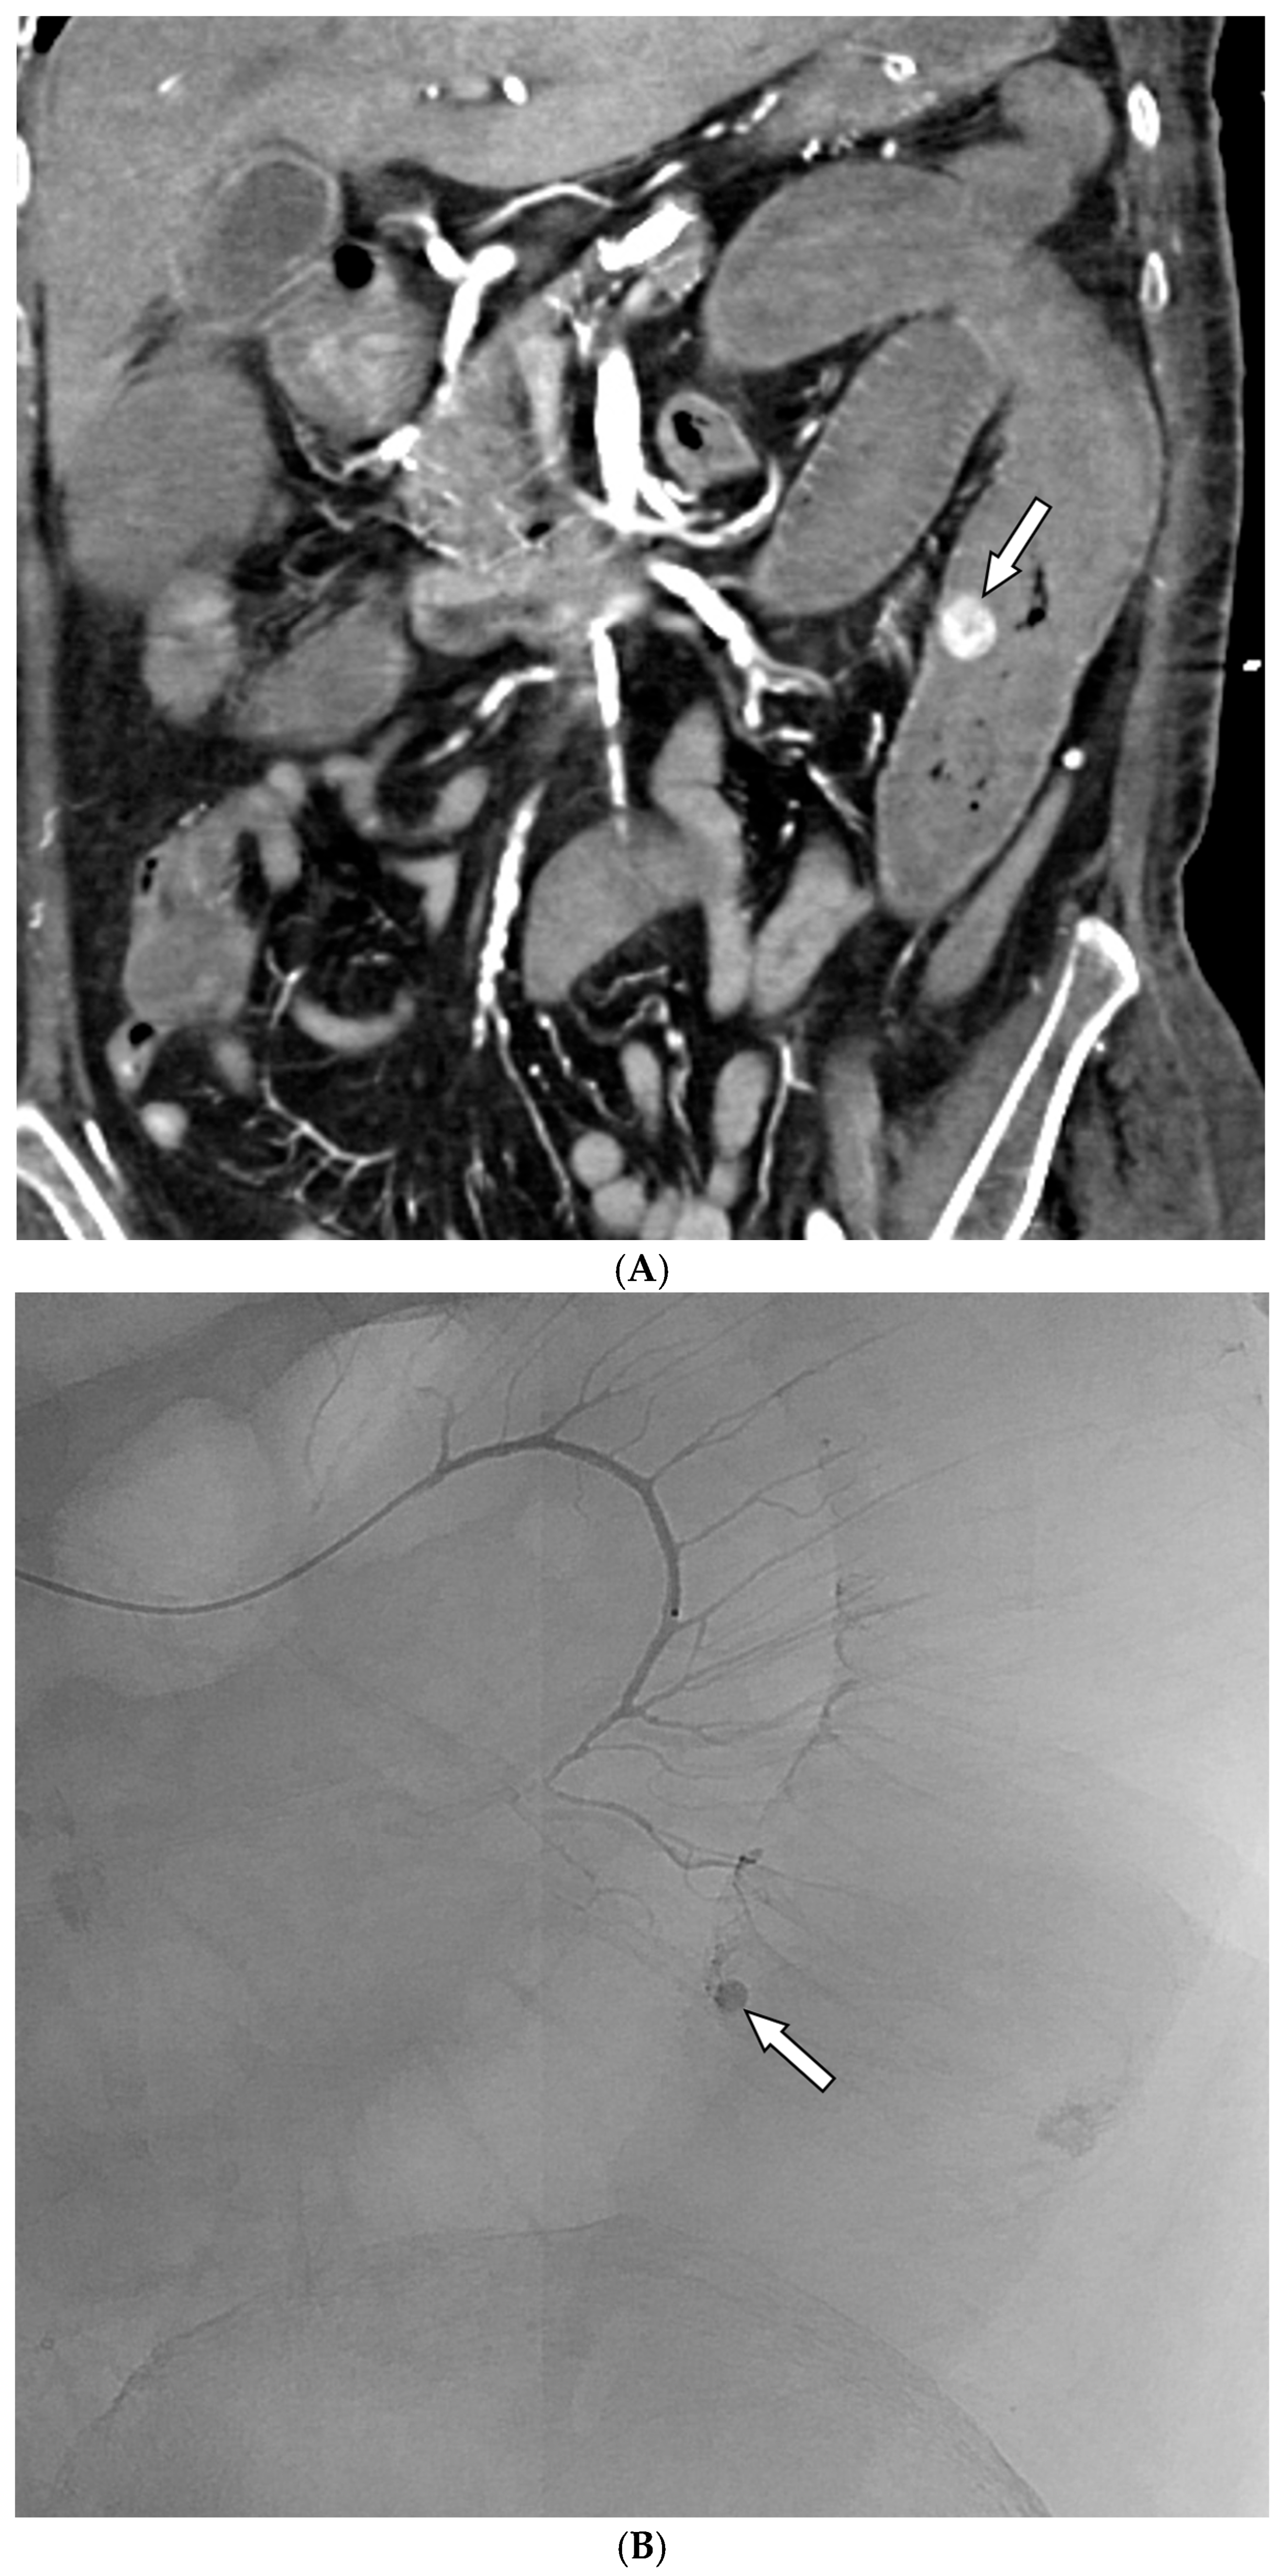

- Alali, M.; Cao, C.; Shin, J.H.; Jeon, G.; Zeng, C.H.; Park, J.-H.; Aljerdah, S.; Aljohani, S. Preliminary report on embolization with quick-soluble gelatin sponge particles for angiographically negative acute gastrointestinal bleeding. Sci. Rep. 2024, 14, 6438. [Google Scholar] [CrossRef]